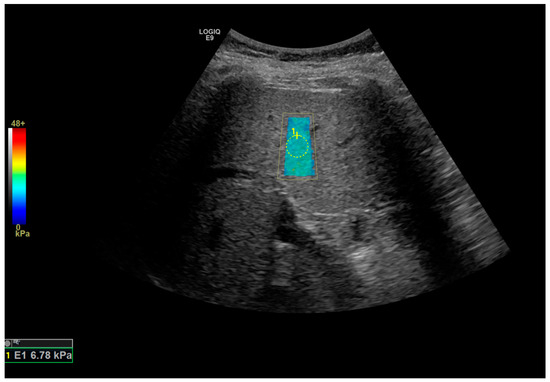

2.2. Assessment of Fibrosis and Steatosis

| Liver stiffness by SWE, mean (SD), kPa | 6.25 (1.04) | 8.33 (2.13) | 0.063 |

| Liver stiffness by TE, mean (SD), kPa | 6.39 (1.03) | 15.17 (5.67) | 0.012 |

| SWE | 8.9 | 75 (62.5–87.5) | 33.3 (0–66.7) | 100 (100–100) | 100 (100–100) | 71.4 (62.5–83.3) |

| TE | 8.5 | 87.5 (68.7–100) | 83.3 (50–100) | 90 (70–100) | 83.3 (57.1–100) | 90 (72.7–100) |